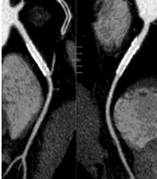

肝脏、胰腺、肾脏CT-DSA 及灌注功能一站式检查

泌尿系成像 肺动脉栓塞 肺透明成像